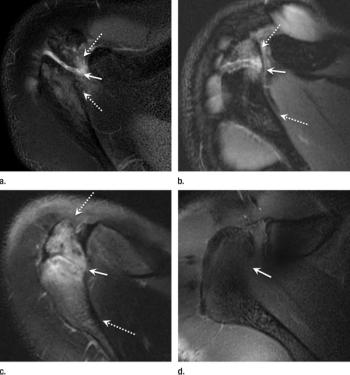

MRI identifies unique shoulder damage, termed acromial apophysiolysis, among young pitchers that could cause long-term problems.